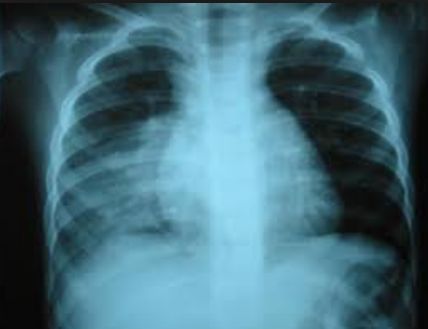

La neumonía alveolar (también denominada lobar, lobular o neumonía segmentaria) es en general causada por patógenos bacterianos, y Streptococcus pneumoniae en particular, sobre todo cuando se acompaña de recuento elevado de leucocitos periféricos, las concentraciones de proteína C reactiva (PCR) y fiebre alta, lo que justifica el tratamiento con antibióticos.

Para aumentar la probabilidad diagnostica de neumonía bacteriana, y minimizar la variabilidad entre los pacientes, se utilizaron criterios de selección predefinidos, que incluían radiografía de tórax, la temperatura corporal y hallazgos de laboratorio.